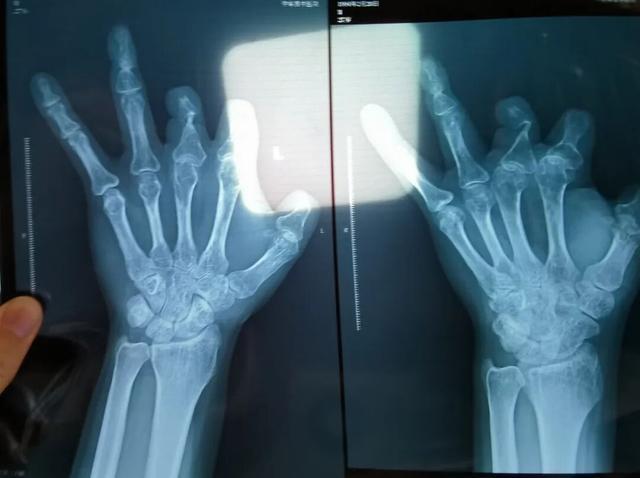

王海森称,他出院约1年后,有人曾找到他说,这个价格昂贵的进口器材,并没有在手术中使用。当时他没有相信,直到2021年12月,经人提醒,王海森在老家开封尉氏县人民医院拍摄了左手X光片,才确认手术部位的确没有微血管吻合装置。2021年12月底,王海森向郑州市公安局二七分局刑侦大队报案。

患者王海森左手拇指关节以上部位被电锯切断,收费单显示术中使用了微血管吻合装置,但X光片中未显示该器械。新京报记者 程亚龙 摄

装置上带有不锈钢针,不可能被人体吸收,唯一的可能就是“手术时其实没有使用”。尽管之前也有其他人向王海森透露过这一点,但直到看到片子前,他一直都不相信。

单价1.68万元,声称在术中植入体内、用于缝合血管的两个环形吻合装置,竟然在王海森的X光片上消失了。

该产品的代理商曾向新京报记者证实,微血管吻合装置为植入型医疗器材,患者拍摄X光片时会有显示。新京报记者获取了一位曾在郑大一附院接受手术、使用了该产品的患者的X光片,其手术部位可见一绿豆大小的光圈。